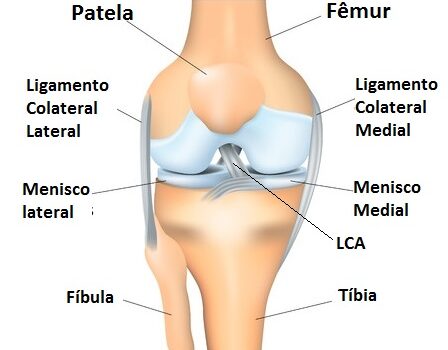

Antes de mais nada, procurar um cirurgião especialista em joelho representa a melhor decisão para pacientes que sofrem com dores crônicas, lesões esportivas ou degenerativas nessa articulação. Dessa forma, a avaliação adequada permite identificar a origem do problema e definir o tratamento mais eficaz para cada situação. Quando procurar um […]

Antes de mais nada, a cirurgia de menisco representa uma das soluções mais indicadas para pacientes que sofrem com lesões no joelho e não obtêm melhora com tratamentos conservadores. Dessa forma, o procedimento devolve mobilidade, reduz a dor e permite que a articulação volte a funcionar de maneira eficiente. Quando […]

Antes de mais nada, a artroscopia no joelho representa uma técnica moderna e minimamente invasiva que auxilia no diagnóstico e tratamento de diferentes lesões articulares. Dessa forma, pacientes que sofrem com dores persistentes, inflamações ou limitações de movimento encontram nesse procedimento uma alternativa segura e eficaz. Indicações da artroscopia no […]